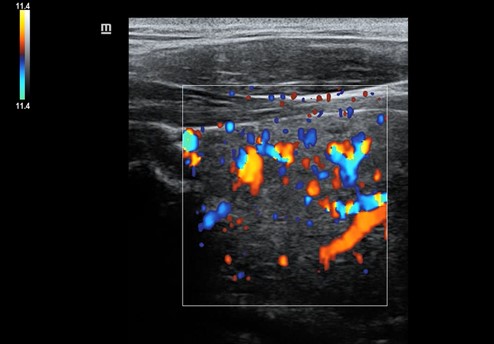

Una vez realizada la anamnesis y la exploración física, se decide realizar una ecografía clínica en la consulta, donde se objetiva un aumento difuso de tamaño del lóbulo tiroideo derecho (33,9 x 38,7 mm), levemente hipoecogénico, con áreas anecoicas en su interior y adenopatías asociadas. Se aplica Doppler color resultando positivo.

El juicio clínico es de una tiroiditis aguda, por lo que se deriva al paciente a urgencias hospitalarias. En urgencias se solicita una analítica sanguínea en la que destaca Leucocitos 7,34 x 103 y PCR 68 mg/L; y una ecografía reglada donde se informa de «tiroides aumentado de tamaño a expensas de lóbulo tiroideo derecho con alteración de la ecogenicidad del parénquima que sugiere proceso infiltrativo afectado al lóbulo derecho, istmo y región anterior del lóbulo izquierdo, no pudiendo apreciar etiología infiltrativa o tumoral».